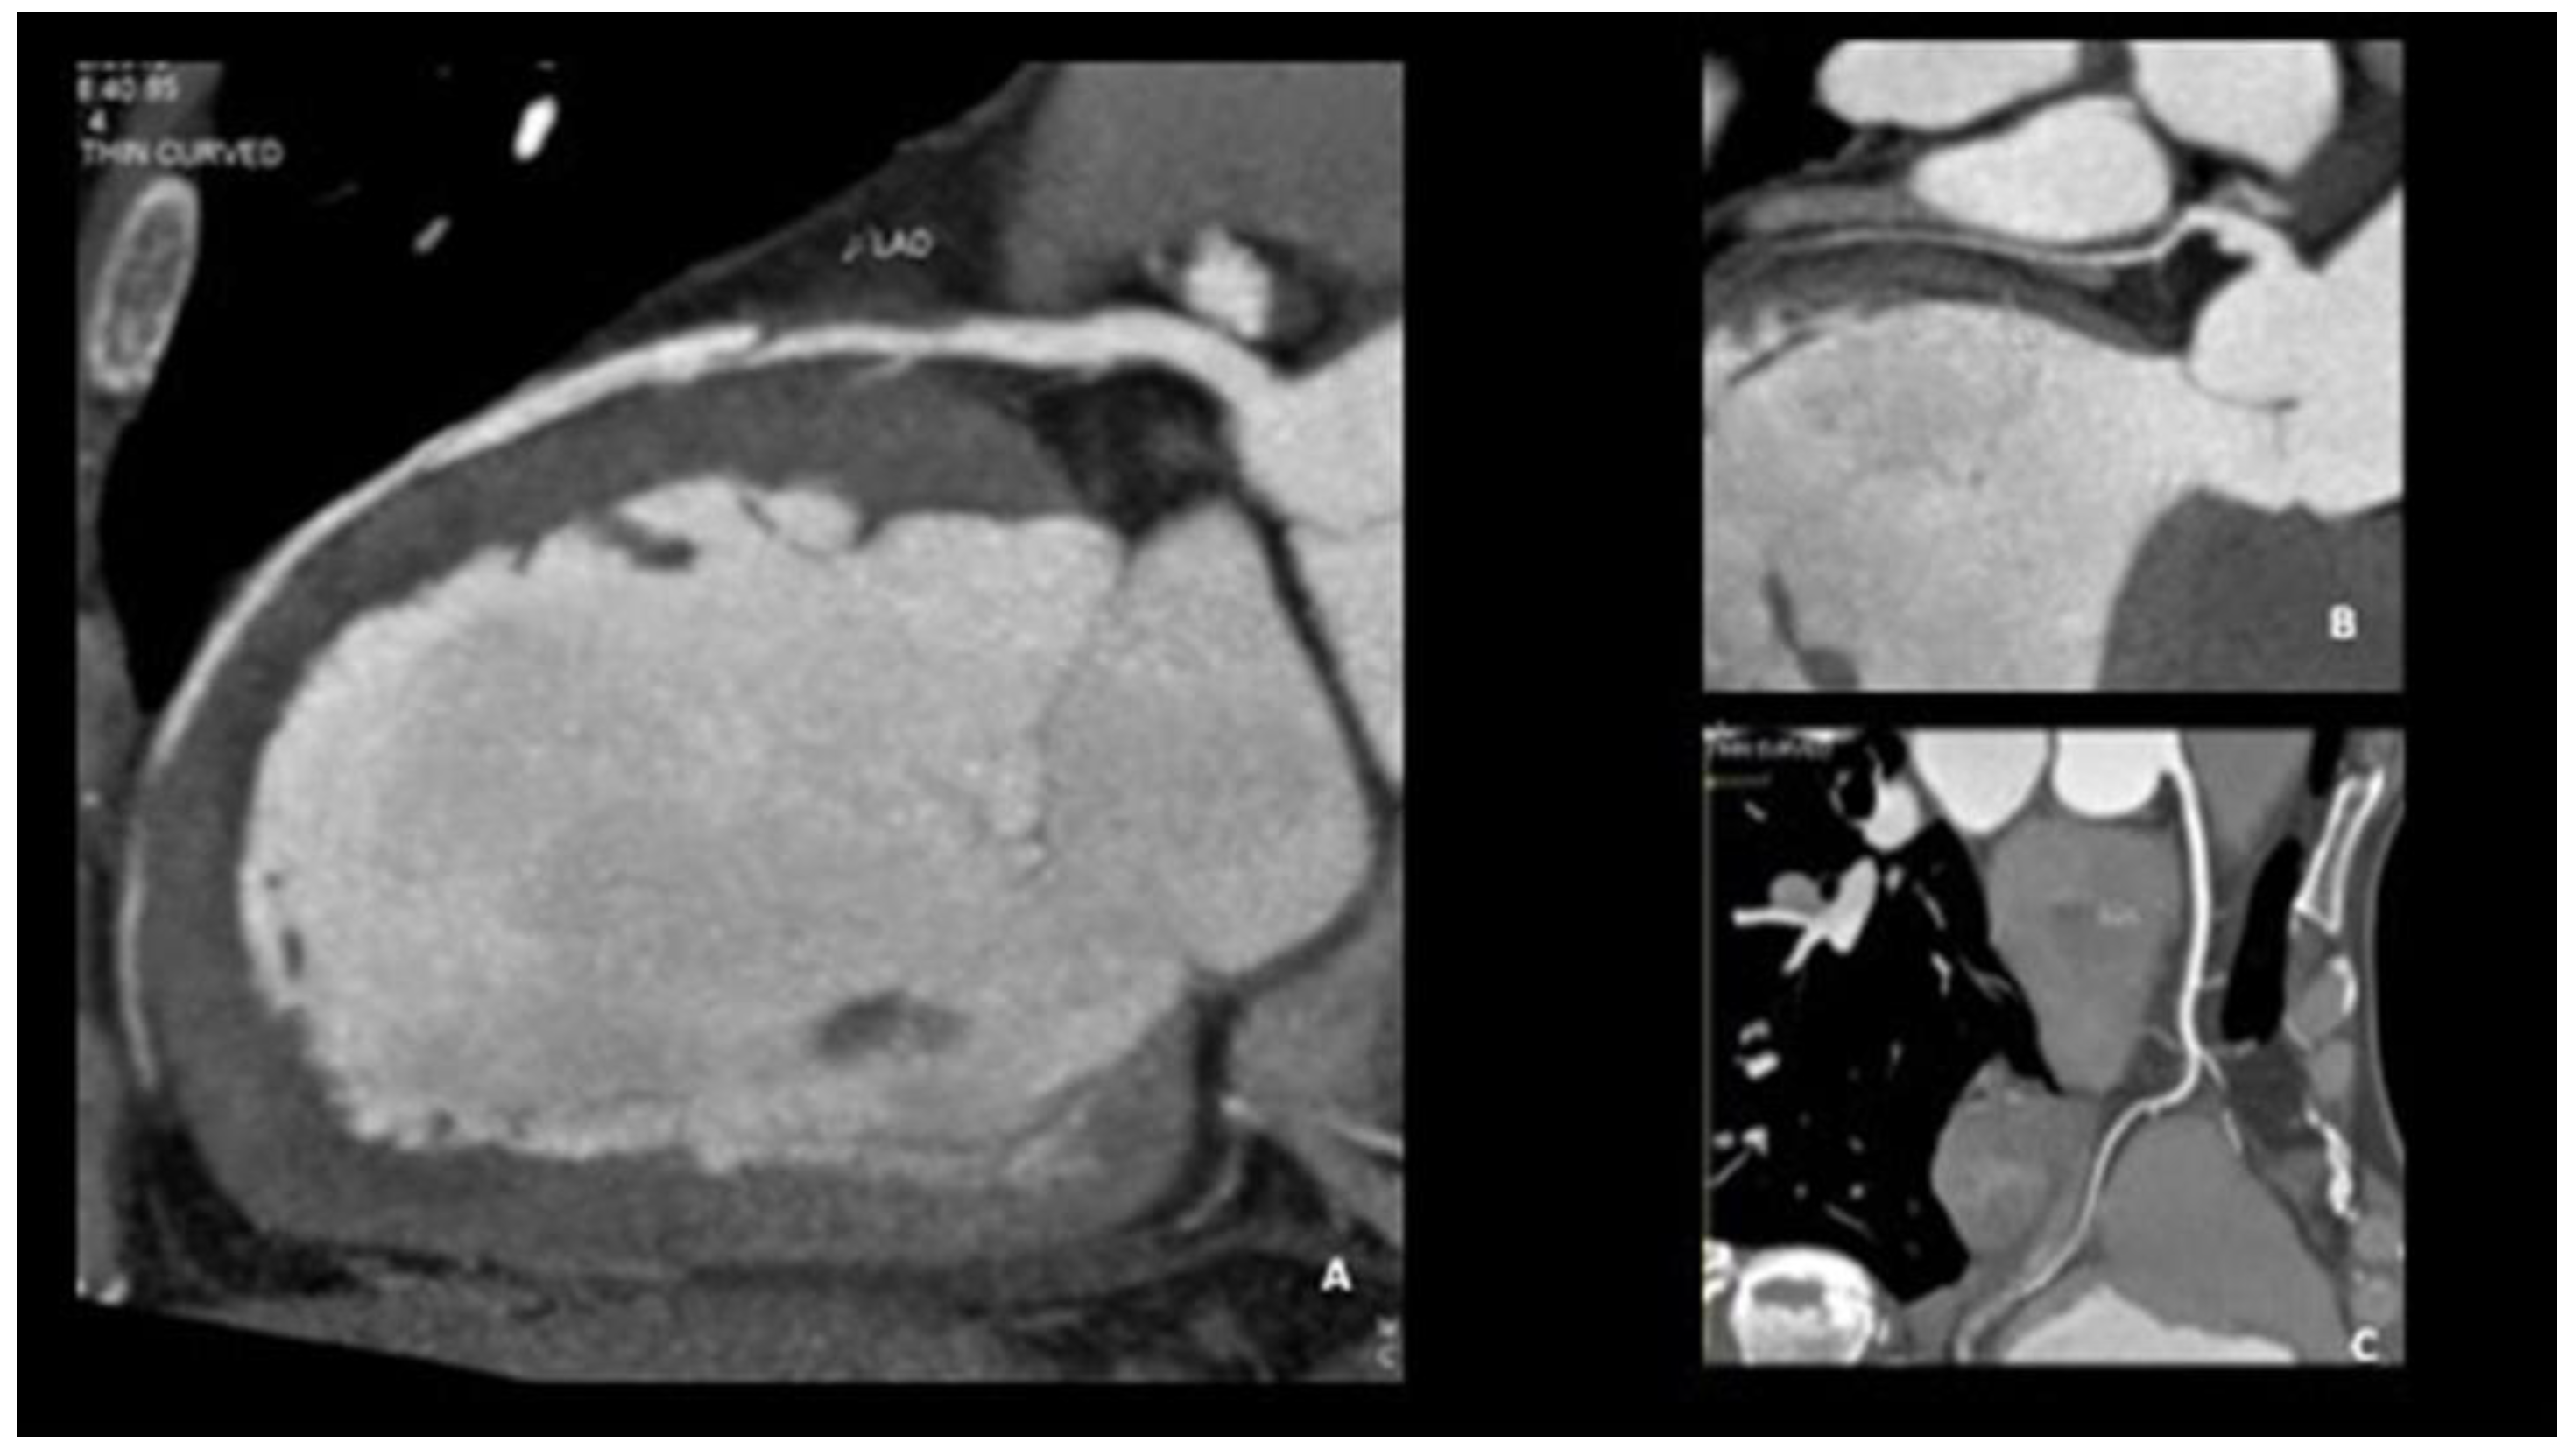

| Coronarography | IVUS | OCT | CCTA | |

|---|---|---|---|---|

| Advantages | Easily executable Images suggestive of SCAD in most cases | Visualization of the intramural hematoma and the flap | Visualization of the vessel wall, the intimate, the false light, intramural hematoma, and any flaps and areas of communication between the true and false lumen | No possibility of iatrogenic damage Image of the presence of contrast in the false lumen Visualization of intramural hematoma |

| Limitations | Invasive Image of the vase light but not the wall | Passage of the guide in the coronary artery No identification of the middle intimal membrane No identification of small areas of connection between false and true lumen | Passage of catheter in coronary artery and injection of contrast at high pressure, with the danger of expansion of the dissection itself | Limited data on its use in acute Absence of specific diagnostic criteria for EXP Frequency-dependent motion artifacts Limited utility for pots < 2.5 mm in diameter Difficulty in distinguishing between non calcified atherosclerotic plaques and intramural hematoma |

| Use | Diagnosis of SCAD | Confirmation of diagnosis | The gold standard method for the confirmation of SCAD | Follow up |